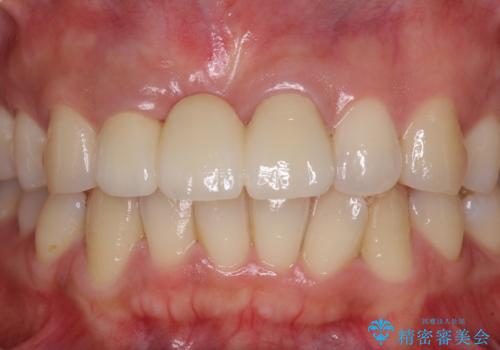

歯肉移植により歯肉ラインや歯の形態を整えることができ、ブリッジによる補綴としたことで舞えば全体の色調を整えることができました。